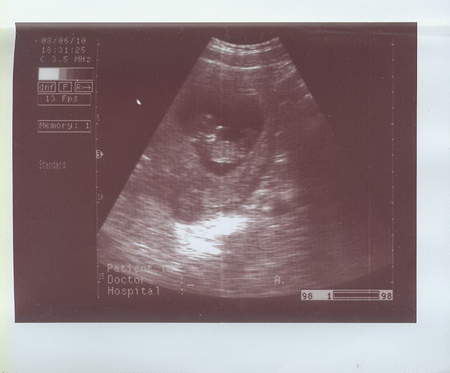

Были на УЗИ 08.06.2010 в МедЦентрСервисе на Курской. Очень понравилось.

С малышом все в порядке, размеры соответствуют норме. Толщина воротниковой зоны 1мм.

Сказал, что Малыш непоседа :) Кувыркался там, как акробат настоящий :)

Срок по УЗИ - 10 недель 3 дня.

Распечатал три фотографии!